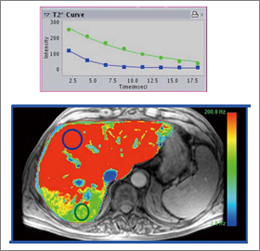

また機能的な部分では,Multi EchoのSegmented Fast GREをベースとしたシーケンスで撮像した画像から,T2減衰の違いをカラーマップ化し(R2マップ),組織内鉄沈着の評価を行うことが期待される(図11)。

図11 肝臓内の鉄沈着の分布を表すR2*マップ

図11 肝臓内の鉄沈着の分布を表すR2マップ